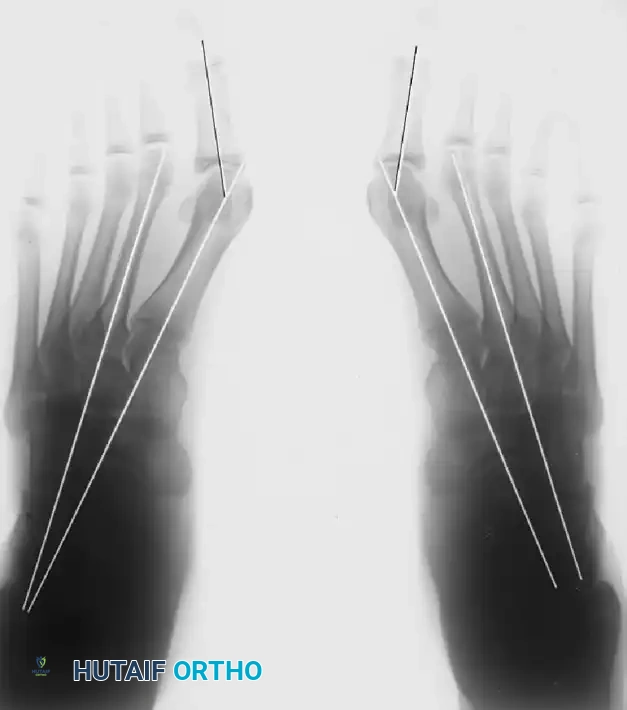

Preoperative standing radiographs of an adolescent with severe hallux valgus and metatarsus primus varus.

Postoperative standing radiographs following proximal osteotomy, adductor tendon release, medial capsular imbrication, and medial eminence removal. Note the incongruous MTP joint on the right, likely resulting from overcorrection of the intermetatarsal angle without addressing the DMAA.